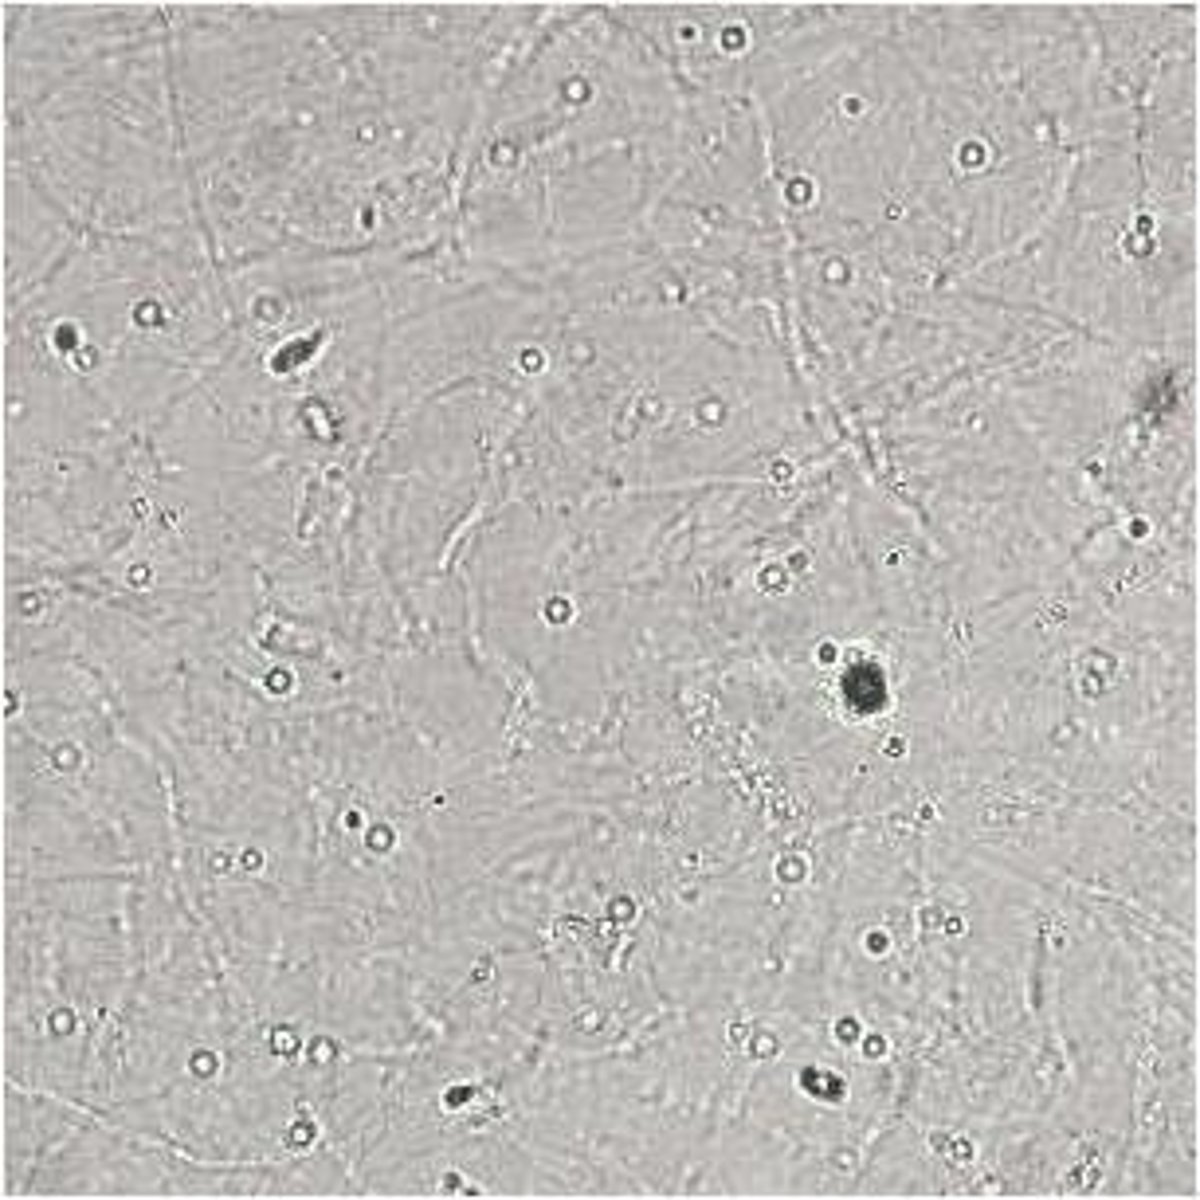

How should you start evaluating urine sediment on the microscope?

Start under low power to evaluate larger elements, then move to 40x to detect bacteria and differentiate cell types

How are epithelial cells, RBCs, and WBCs reported in urinalysis?

Reported per high power field

How are bacteria reported in urinalysis?

Reported as few, moderate, or many and morphology

Normal constinuents of urine sedmient

Few casts, crystals, epithelial cells, RBCs and WBCs, mucus threads and sperm, fat droplets

Abnormal constituents of urine sediment

More than a few RBCs and WBCs, hyperplastic or neoplastic epithelial cells, casts, crystals, parasite ova, bacteria, and yeast